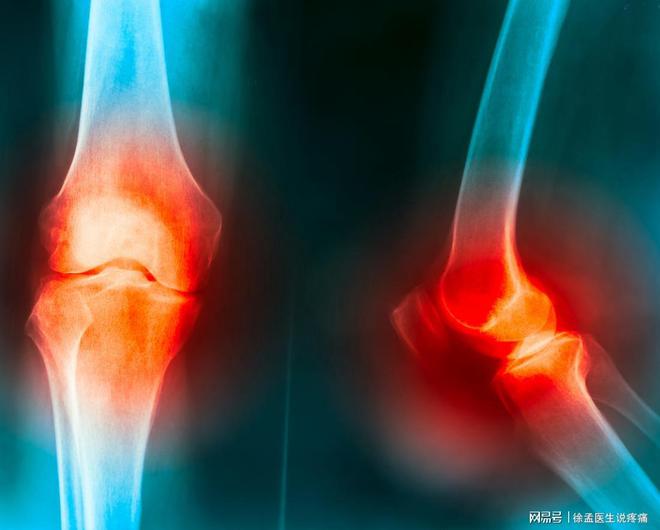

중국이 고령화 사회에 접어들면서 퇴행성 관절염의 발생이 증가하고 있는데, 퇴행성 관절염이란? 누가 쉽게 얻을 수 있습니까? 이를 예방하고 완화하는 방법은 무엇입니까? 한 번 보자!

퇴행성 관절염은 흔히 골관절염이라고 부르는 질환이다. 간단히 말해서 관절의 연골이 서서히 닳아 없어지는 것입니다. 연골은 매우 매끄러운 물질로 관절 끝을 덮고 윤활유처럼 관절이 부드럽게 움직일 수 있도록 도와주며 연골이 마모되면 뼈가 서로 직접 마찰하여 통증, 부종을 유발할 수 있으며 관절을 뻣뻣하고 덜 매끄럽게 만들 수도 있습니다.

시간이 지남에 따라 연골이 마모되는 것은 자연스러운 노화의 일부이지만 관절의 과도한 사용, 부상 또는 과체중으로 인해 가속화될 수도 있기 때문에 일반적으로 나이가 들면서 발생합니다. 한마디로 퇴행성 관절염은 연골의 마모로 인해 관절의 사용이 어려워지는 질환이다.